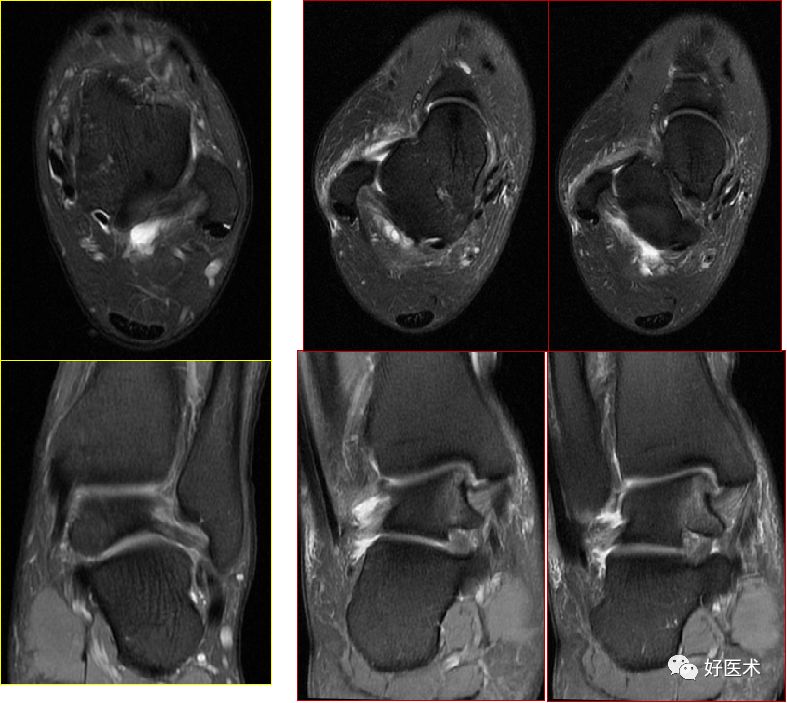

三、骨软骨病变

距骨骨软骨损伤,好发于前外侧、后内侧,尤其是后内侧,与内外翻损伤相关。

距骨骨软骨损伤分级